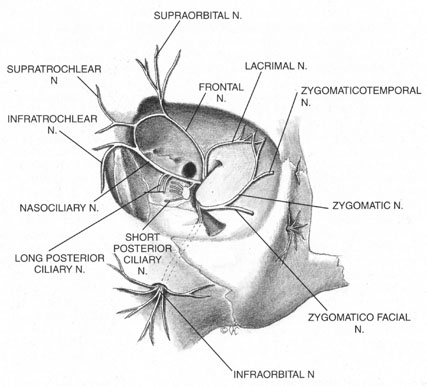

The trigeminal nerve carries the sensory innervation of the eye and adnexa in three divisions: ophthalmic, maxillary, and mandibular. Except for a portion of the sensory input from the lower lid that is carried by the maxillary division, the sensory fibers of the eye and adnexa are found in the ophthalmic division. This division in turn has three components: frontal, lacrimal, and nasociliary, as shown in Figure 1. The frontal nerve usually branches into two more divisions: the supraorbital, which carries sensation from the conjunctiva and skin of the central two-thirds of the upperlid; and the supratrochlear, which carries sensory fibers from the medial third of the upper lid. The lacrimal nerve carries sensory input from the skin and conjunctiva of the lateral aspect of the upper lid.47 The nasociliary nerve carries sensory fibers from the cornea, iris, ciliary body, perilimbal bulbar conjunctiva, and optic nerve sheath; these fibers proceed through its long ciliary branches and sensory root to the ciliary ganglion. The infratrochlear branch of the nasociliary nerve carries sensory input from the medial canthus, medial portion of lower lid skin and conjunctiva, caruncle, lacrimal sac, and canaliculi.

Once it is known which branches are responsible for carrying sensory input from which structures, an approach can be planned that has a reasonable chance of blocking the targeted area. Because, for example, the nasociliary nerve carries fibers that pass through the intraconal space, a standard intraconal retrobulbar block may provide excellent intraocular and partial surface anesthesia. It could not be expected, however, to effectively block the conjunctiva of the upper or lower lids or the lateral aspect of the globe. Because the frontal and lacrimal branches enter the orbit through the superior fissure, above the annulus of Zinn, and the maxillary division enters the orbit through the infraorbital foramen, below the annulus, an intraconal approach probably would not effectively block the structures these branches innervate. If an intraconal retrobulbar block is the only one administered before surgery, patients can be expected to feel irrigating solutions being dropped on the conjunctiva, away from the limbus; they also will be aware of the lid speculum and any manipulation of the lateral surface of the globe. They will probably attempt to close the eye in response to these stimuli. This is the basis for the traditional facial–retrobulbar block combination.

As has been mentioned, numerous facial blocks have been devised to prevent patients from squeezing the eye shut during surgery. None of these blocks keeps patients from wanting to close the eye—only from succeeding. Because the facial block also involves added discomfort, many anesthesiologists and surgeons provide intravenous sedation along with it. Thus, limiting the initial block to the intraconal retrobulbar space also limits its potential benefits, requiring two supplemental procedures. Anatomy determines effect.

The anterior blocks—peribulbar, parabulbar/sub-Tenon's, and topical—reduce or eliminate the need for a separate facial block by providing better surface anesthesia than the retrobulbar block. Although the first two also provide intraocular anesthesia through their effect on the nasociliary branch, topical blocks provide only surface anesthesia, so that intraocular sensations, such as stretching of the zonules during filling of the anterior chamber, may be felt throughout surgery. Some authors advocate the addition of a subconjunctival injection to add more anesthetic effect to a topical block.48 Recently, intraocular injections of local anesthetics have been popularized as an adjunct to topical anesthesia. This technique is discussed later in this chapter.